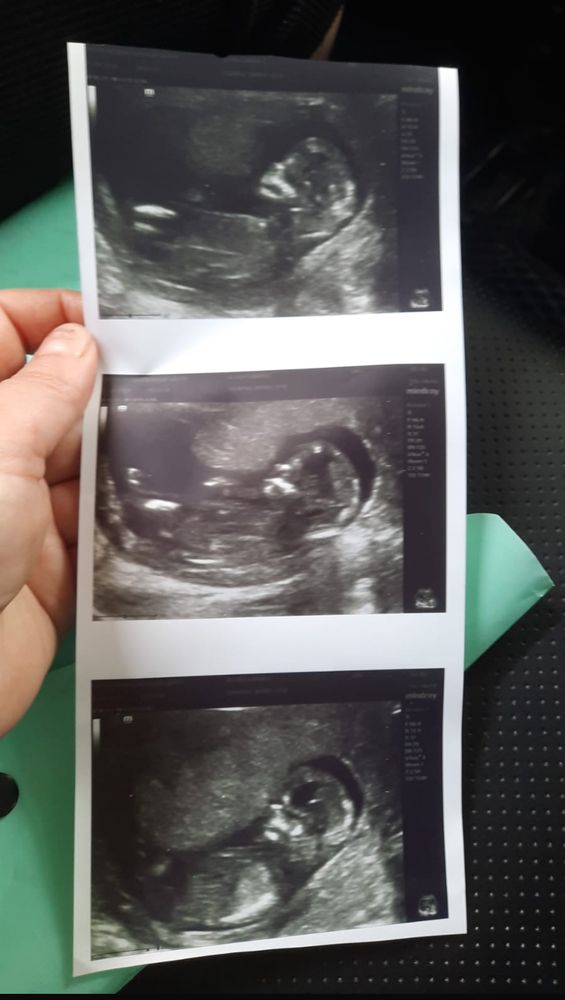

Здравствуйте девушки как думаете кто у нас мальчик или девушка

Как тут не видя причинного места можно определить... У девочек бугорок торчит условно вдоль тела, у мальчиков торчит под углом больше вверх.

У вас не видно полового бугорка, по этому навряд ли кто то из нас может определить, ракурс не тот. А вам врач не предположила пол на узи ?

По голове пол сказать?)